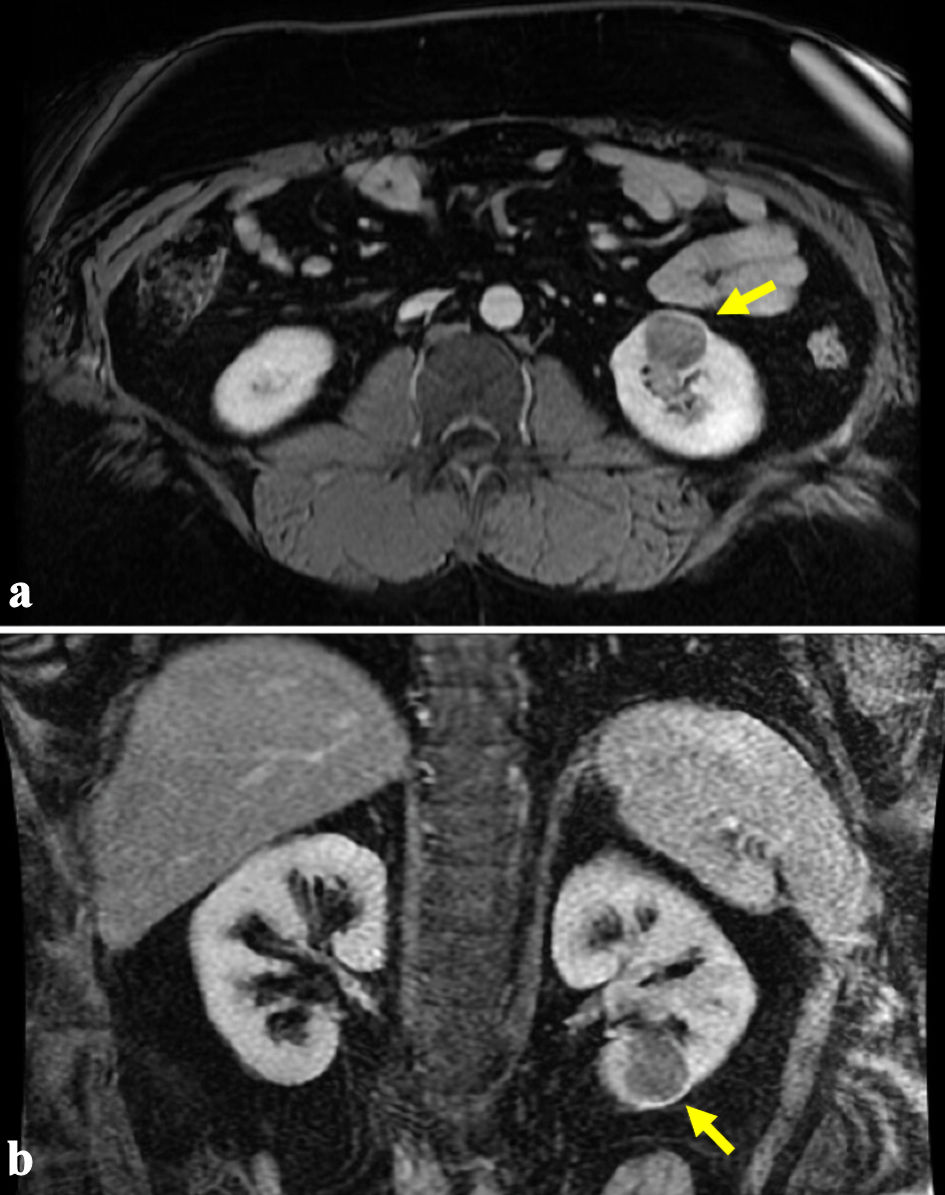

The patient is a 38-year-old male referred to our tertiary care center for management of a renal mass. He initially presented to an outside institution with gross hematuria where an office cystoscopy was performed, which was unremarkable. Computed tomography (CT) showed a 3.1-cm soft-tissue density in the lower pole of his left kidney (Fig. 1), and magnetic resonance imaging (MRI) confirmed a 2.8 × 2.5 × 2.9 cm enhancing left renal mass (Fig. 2). Notable medical history includes class III obesity with a BMI of 57.9 kg/m2 (Table 1). After thorough counseling on the etiology, evaluation, and management of small renal masses, including increased risk of musculoskeletal complications related to his obesity, the patient selected robotic-assisted partial nephrectomy as his preferred treatment.

Figure 2. (a, b) Representative magnetic resonance imaging (MRI) demonstrating an enhancing 2.8 × 2.5 × 2.9 cm left renal mass as indicated by the arrows.